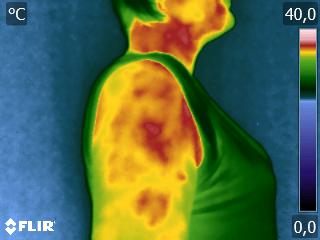

Dra. Paula Machado e Eng. Attílio Veratti.

#fisioterapia #termografia #termografiainfravermelha #feliznatal